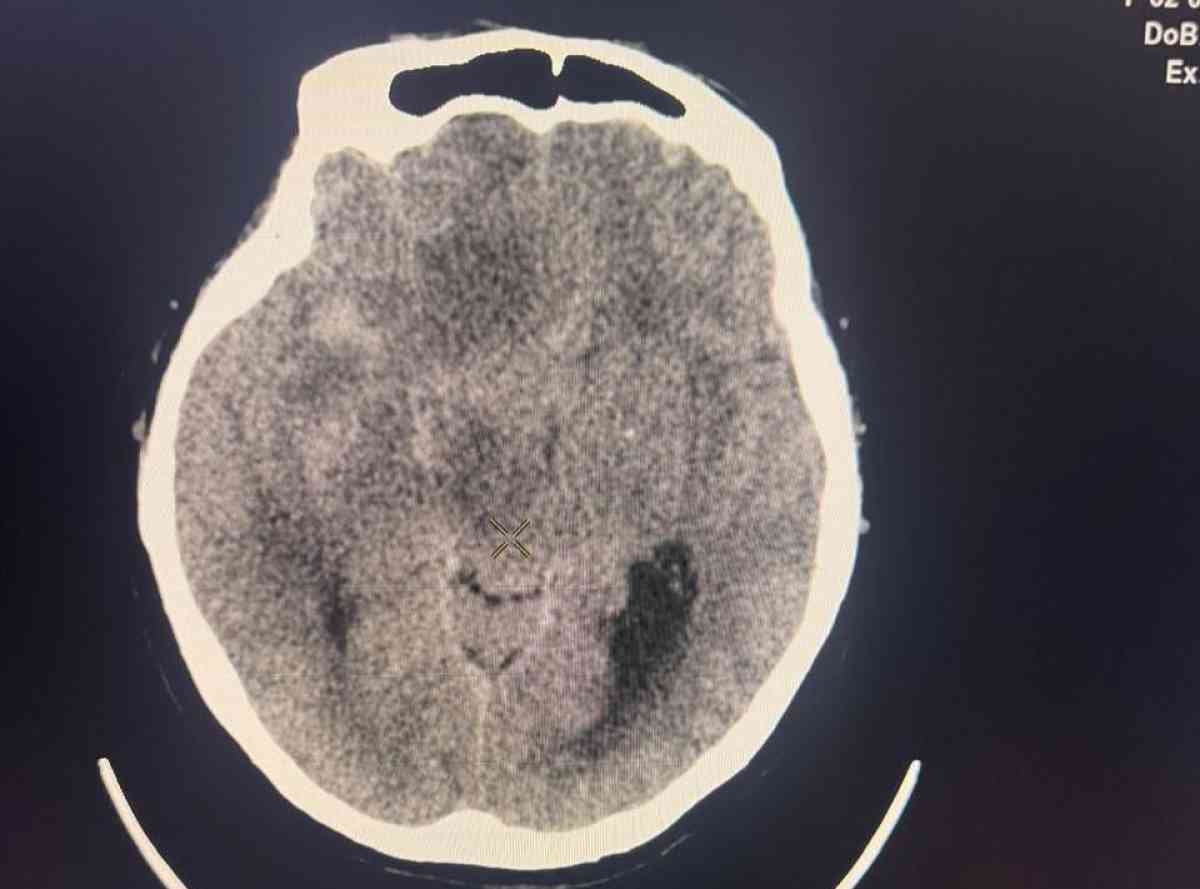

1965 жылы туған пациент Т. ауруханаға өте ауыр жағдайда — жедел инсульт және миға қан құйылу диагнозымен жеткізілген. Компьютерлік томография кең көлемді трепанацияны талап еткен: ми детриті мен үлкен көлемдегі қан ұйындыларын алу керек болған.

Алайда жаңа технология жағдайды түбегейлі өзгертті. Орындалған бас ішілік қысымды бақылау мен уақтылы жүргізілген коррекция арқасында мамандар жарақаттаушы операциядан бас тартып, науқастың жағдайын тұрақтандыра алды. Ми ісігінің асқынуы болдырылмай, кешенді ем нәтижесінде пациент аман қалды. Қазіргі таңда ол үйіне шығарылып, оңалтуды жалғастыруда.